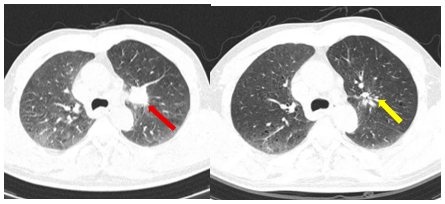

Hình 4.

Hình ảnh phim chụp cắt lớp vi tính ngực ngày 10 tháng 7 năm 2025 (mũi tên vàng) so với ngày 19 tháng 03 năm 2025 (mũi tên đỏ), kích thước khối u giảm đáng kể so với phim chụp cũ.